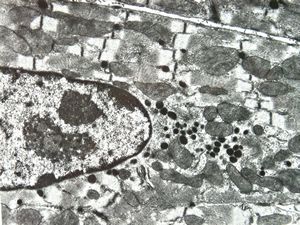

M, 7w. | mitochondrial cardiomyopathy (N - nucleus, M - megamitochondria,R - dilated endoplasmic reticulum)- autopsy sample